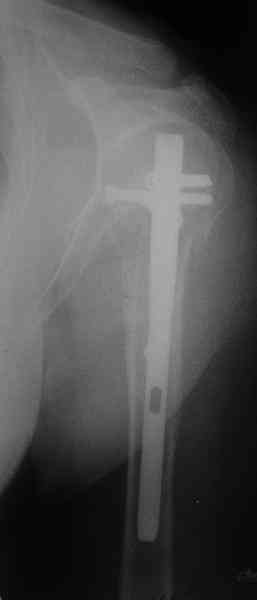

I am attaching the radiographs of the mother of a doctor. She has chronic renal failure for >10 years, diabetes mellitus and coronary artery disease. Age 62. She was offered the options of non-surgical management in a sling and surgery with a locking plate. She was given Tramadol for pain relief. Five days after injury, patient requested surgery, because of pain, inability to move without pain.

The reduction is not perfect. The patient is very small made, and it was difficult to bring the plate proximally without impingement in abduction.

Pain relief after surgery was early and sustained.

I agree that this reduction is not perfect. The gap may later result with nonunion. Such or even better reduction can be reached without site

opening as you mentioned. Locking plates are positioned as less invasive, why so long incision was - even longer than plate?